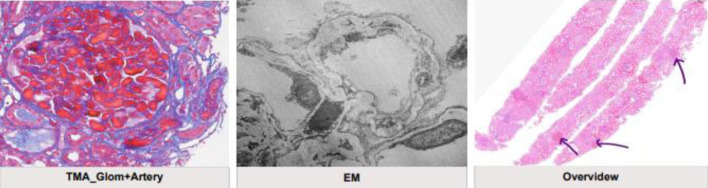

Catastrophic antiphospholipid syndrome (CAPS) is a rare, severe, and life-threatening form of antiphospholipid syndrome (APS). Early recognition and rapid treatment are of great importance to improve patient outcomes and decrease mortality. Herein, we present a case of lupus and APS with obstetric complications, recurrent thrombosis, and renal and hematological manifestations of APS which showed great response to the treatment.

Abstract Image